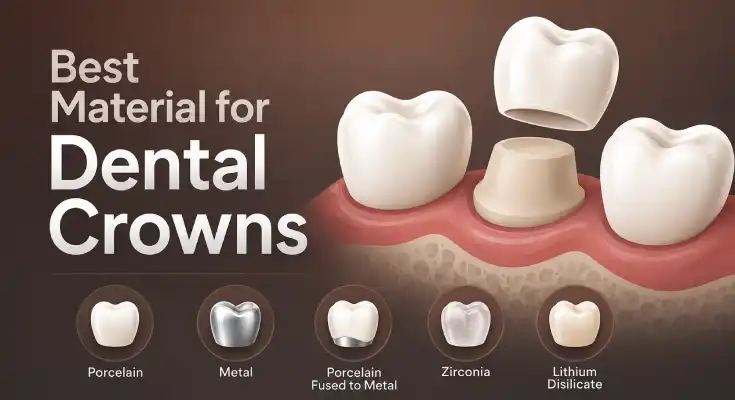

Progressive decay will require more aggressive actions, such as fillings or crowns. These will prevent more tooth damage and loss of function.

Best Material for Dental Crowns: What Actually Works for Your Tooth

Written by Dr. Alexander Heifitz, Founder of AL Dental Studio | Medically Reviewed. Last updated on May 22, 2026.

Read More